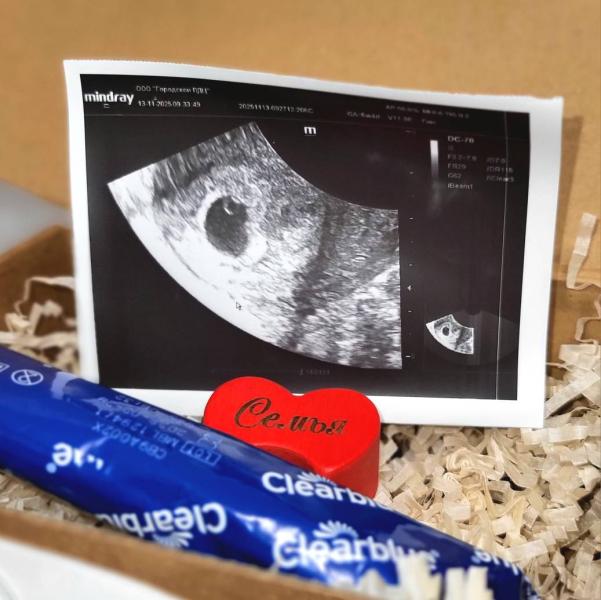

Была сегодня на первом УЗИ. Срок 5,4. Беременность маточная🙏 СВД плодного яйца - 9мм; желточный мешочек - 3,2мм. Но эмбриончика пока нет. Скоро должен появиться. Ушла гулять аж до 2.12⏳ прямо перед приёмом гинеколога. Там уже точно все должно быть🤞 Очень волнительно ждать столько, но мне почему-то не хочется часто бегать на УЗИ как в первый раз.

А пока готовлю мужу сюрприз на его ДР, на завтра. 🤍